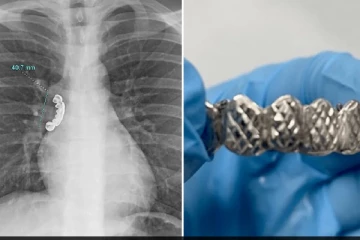

வெள்ளி பற்களை விழுங்கிய இளைஞர்: உயிரை காப்பாற்ற மருத்துவர்கள் மேற்கொண்ட சிகிச்சை